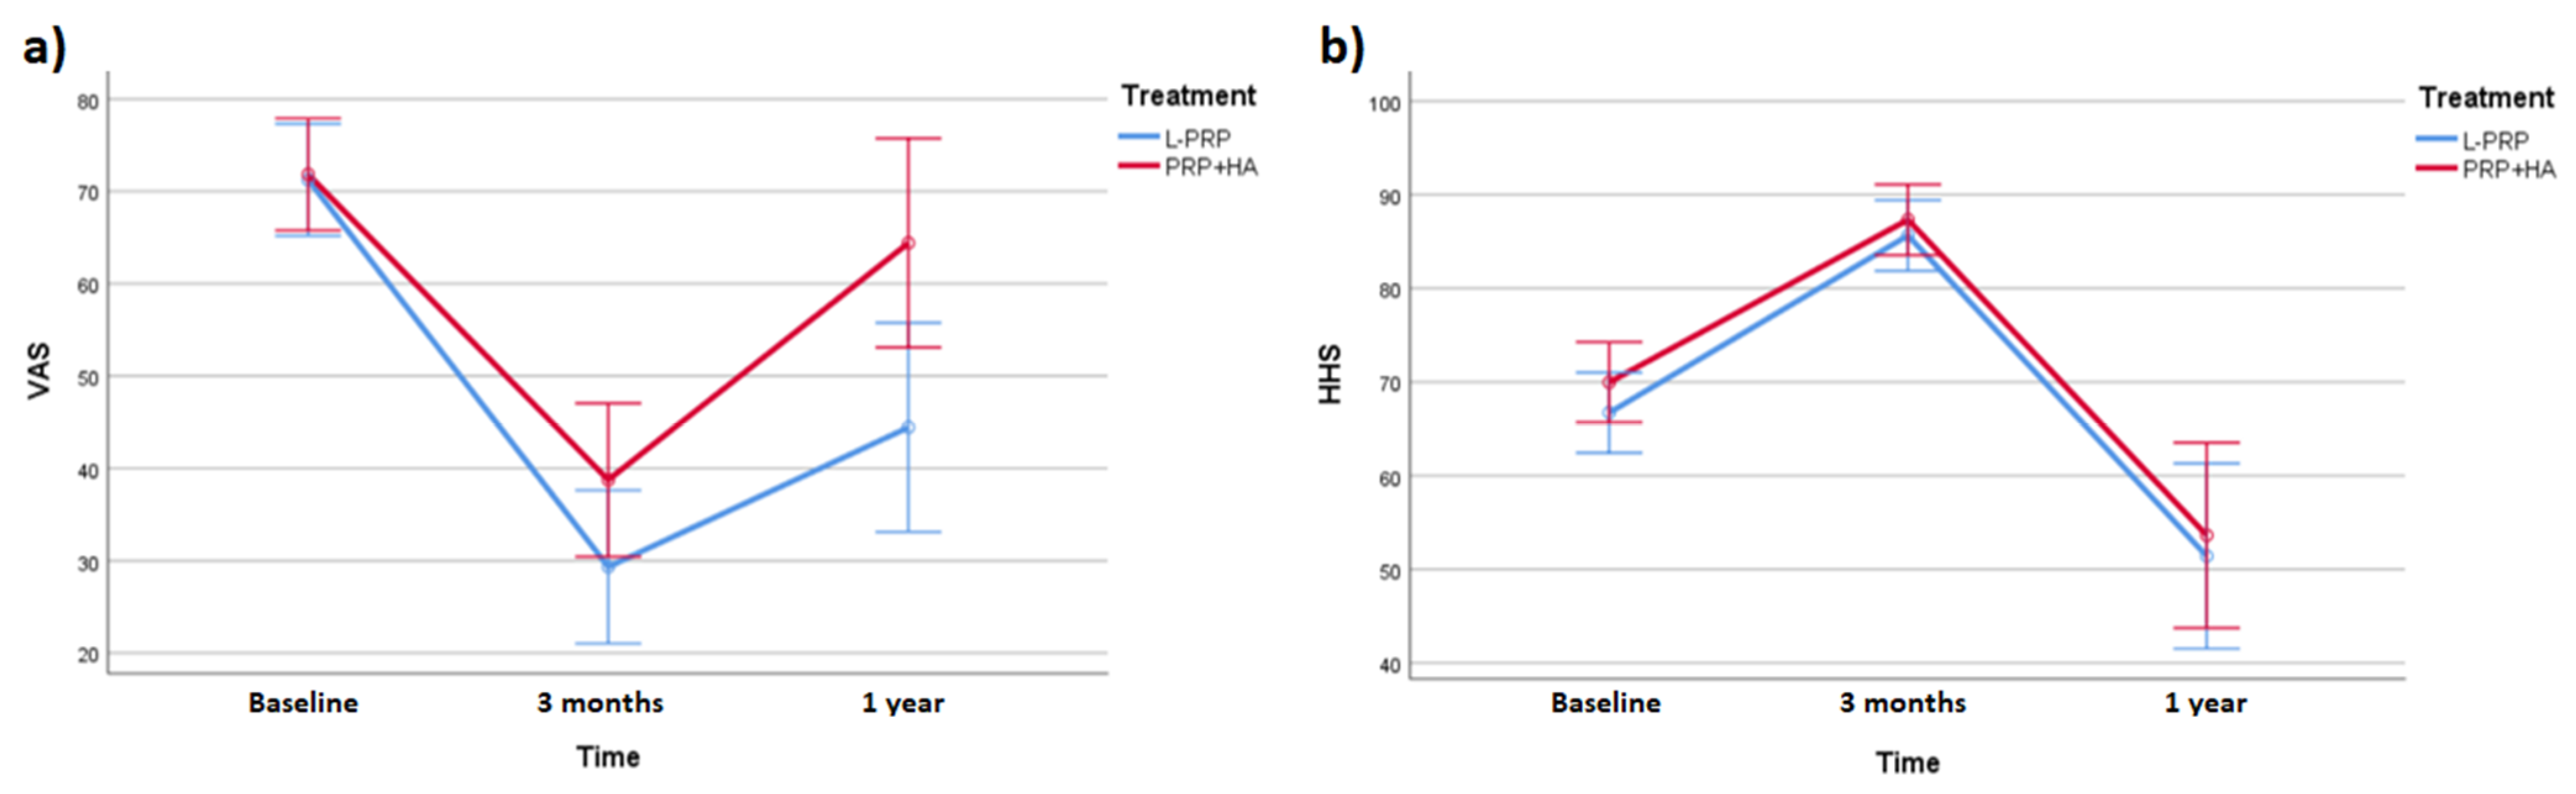

2.2. Efficacy of L-PRP and PRP+HA

2.3. Differences between Treatments

| Baseline | 3 Months FU | 1 Year FU | |

|---|---|---|---|

| VAS (L-PRP) | 72.69 ± 13.65 | 30.00 ± 16.37 | 49.62 ± 14.53 |

| VAS (PRP+HA) | 70.38 ± 15.55 | 38.08 ± 19.90 | 59.23 ± 26.74 |

| HHS (L-PRP) | 66.86 ± 9.96 | 86.09 ± 8.88 | 53.08 ± 24.31 |

| HHS (PRP+HA) | 69.93 ± 10.31 | 86.88 ± 8.88 | 51.97 ± 22.91 |